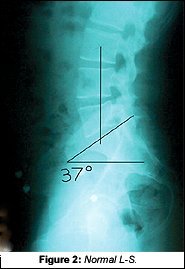

On Tony's x-rays, there were many subtle findings, but the lateral L-S showed more than enough reason for his 10 years of problems. A normal sacral base angle (Figure 2 on page NE-2) would be 36Á-42.Á Tony's lateral L-S (Figure 3) had a 56Á sacral base angle. In addition to this distortion, he also had a severe anterior gravity line. Normal weightbearing should bisect the anterior third of the sacral base.